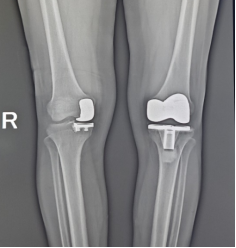

l 半髋、全髋关节置换术及翻修术、全膝关节置换术及翻修术

6. 膝关节置换术